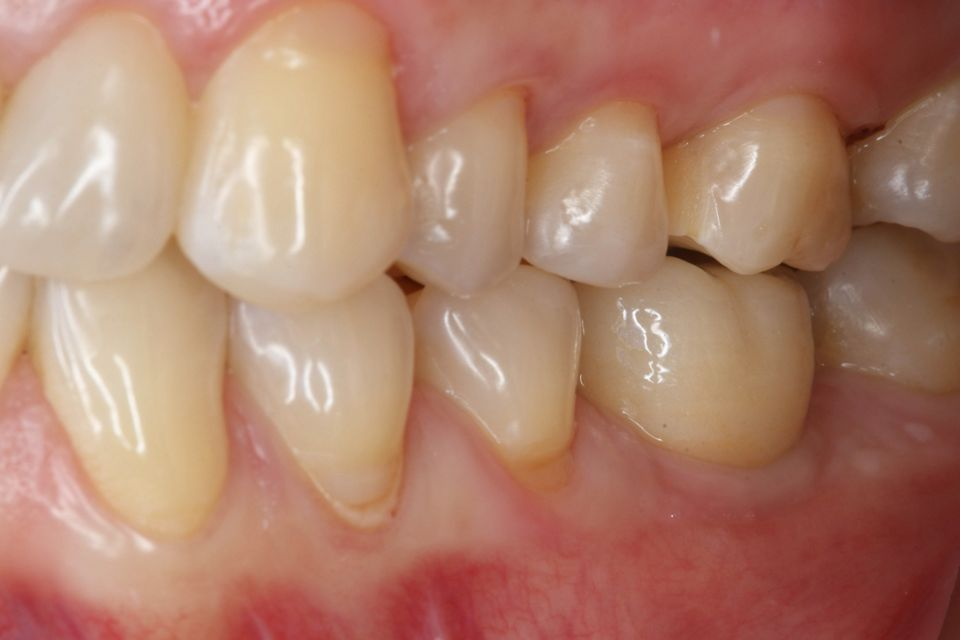

手术后一周,拆线(图11-12)。在同一次就诊时,拍摄了垂直牙科射线照片(图 13),显示种植体处于正确的修复位置。四个月后,愈合基台被移除。粘膜外观表明植入物周围有稳定且健康的软组织,具有足够的生物宽度和光滑的出现轮廓(图14-15)。取印模,一个月后,将最终的氧化锆陶瓷牙冠拧到种植体上(图 16-18)。